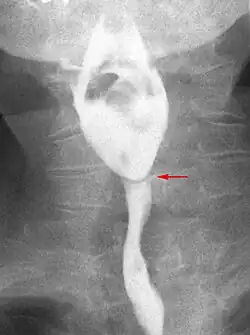

Esophageal web stenosis in barium swallow examination frontal view.

The diagnostic test of choice is a barium swallow.